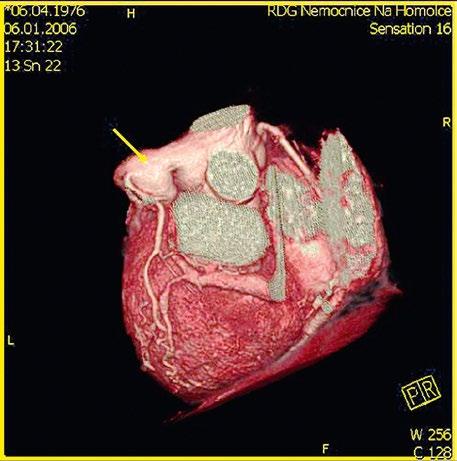

Obr. 45.11 CT angiografie, defekt typu sinus venosus superior je označen hvězdičkou, anomální pravá horní plicní žíla ústící do horní duté žíly je označena šipkou

PS – pravá síň, LS – levá síň

Obr. 45.12 CT angiografie s 3D rekonstrukcí u pacientky s defektem typu sinus venosus superior a s parciálním anomálním návratem dvou pravostranných plicních žil z horního a středního laloku do horní duté žíly, pravá dolní plicní žíla ústí normálně do levé síně